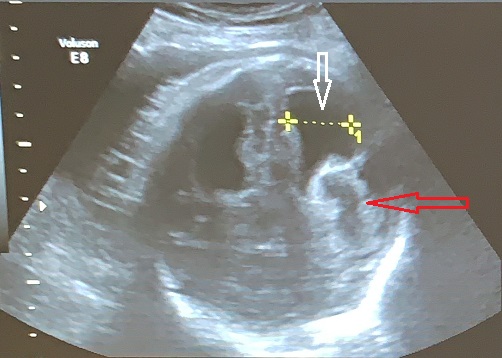

La Neurosonografía Fetal se refiere a la evaluación del Sistema Nervioso Central por Ultrasonidos: cráneo y su contenido (cerebro, ventrículos, tallo, cerebelo, etc.) y de la columna vertebral y su contenido (vértebras, médula espinal, líquido cefalorraquídeo, etc.).

Las estructuras intracraneales después de la semana 18-20 del embarazo son muy características y permanecen visualmente invariables hasta el final del embarazo, solo modificando sus tamaños a medida que el feto crece. Esto es de gran ayuda ya que permite determinar la aparición de cambios que podrían sugerir desviación de la normalidad y aparición de una malformación congénita o lesión adquirida por eventos externos especialmente relacionados a infecciones y accidentes vasculares fetales.

Cuerpo calloso: es una estructura compuesta por haces nerviosos cuya función es la de conectar e integrar regiones corticales homólogas entre ambos hemisferios cerebrales. Su ausencia total puede conducir a problemas cognitivos y del desorrollo psicomotriz o pasar totalmente desapercibida. Su ausencia parcial, paradójicamente, se asocia con peor pronóstico. Como estructura ecográfica, es una de las más bellas que hay en el cerebro pero, para obtenerla se requiere pericia y muy buena resolución ecográfica. Sus alteraciones congénitas son diagnóstico de problemas primarios del desarrollo cerebral y se manifiestan con cambios indirectos en otras secciones cerebrales, especialmente ventriculomegalia.